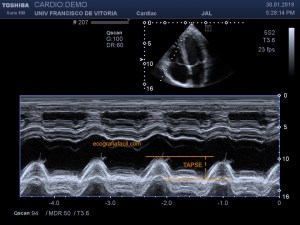

141. Mediciones de los planos paraesternales.